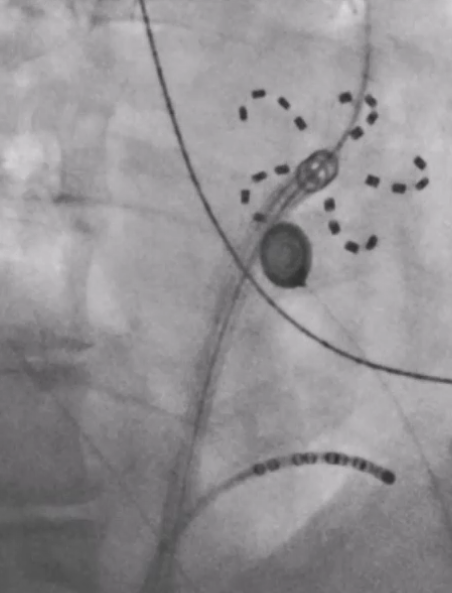

Vorhofflimmer Therapie - persönlich und individualisiert

Vorhofflimmern ist mit Abstand die häufigste Rhythmusstörung - jeder 3. Europäer wird im Laufe seines Lebens daran erkranken. Erfahren Sie mehr, wie wir Vorhofflimmern mit modernster Kathetertechnik behandeln - egal, ob Sie seit kurzem erkrankt sind, oder die Erkrankung bereits chronifiziert ist. Wir finden für Sie die richtige Technologie!

Mehr Lebensqualität trotz fortgeschrittener Herzschwäche

Wir werden älter - und unsere Herzen mit uns zusammen natürlich auch. Immer mehr Patienten leiden an komplexen Herzerkrankungen. Wir bündeln für Sie Expertise - sei es ambulant in unseren Spezialsprechstunden, oder im Rahmen stationärer Behandlungen.